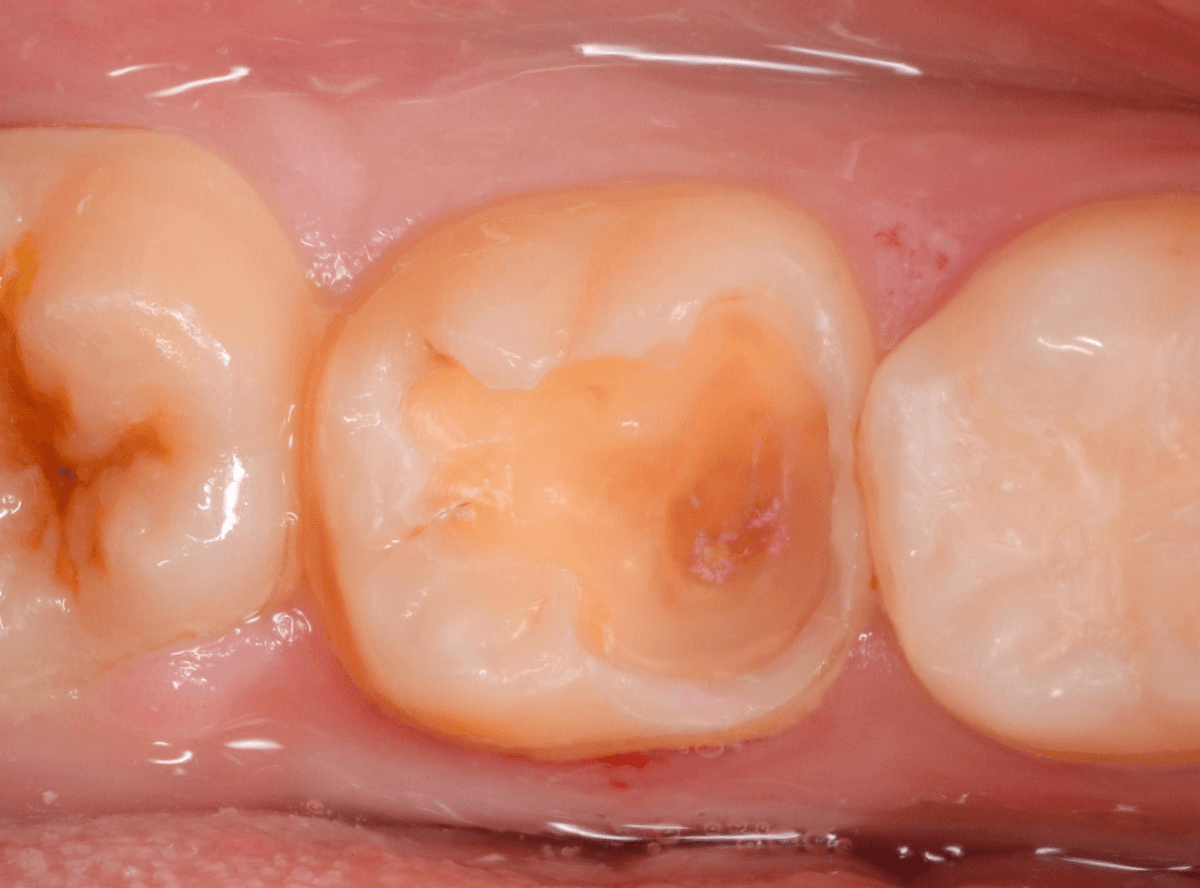

Case.12 検診で見つかった、インレーの下の深い虫歯

検診目的で来院された患者さんです。

特に気になるところもなかったですが、検査をすると、お口の中の色々な部分に虫歯が見つかりました。

その中の一か所、上の奥歯のインレーの下の虫歯です。

見た目だけでははっきりわかりませんでしたが、レントゲン写真で確認すると、インレーの下で虫歯になっているのがわかります。